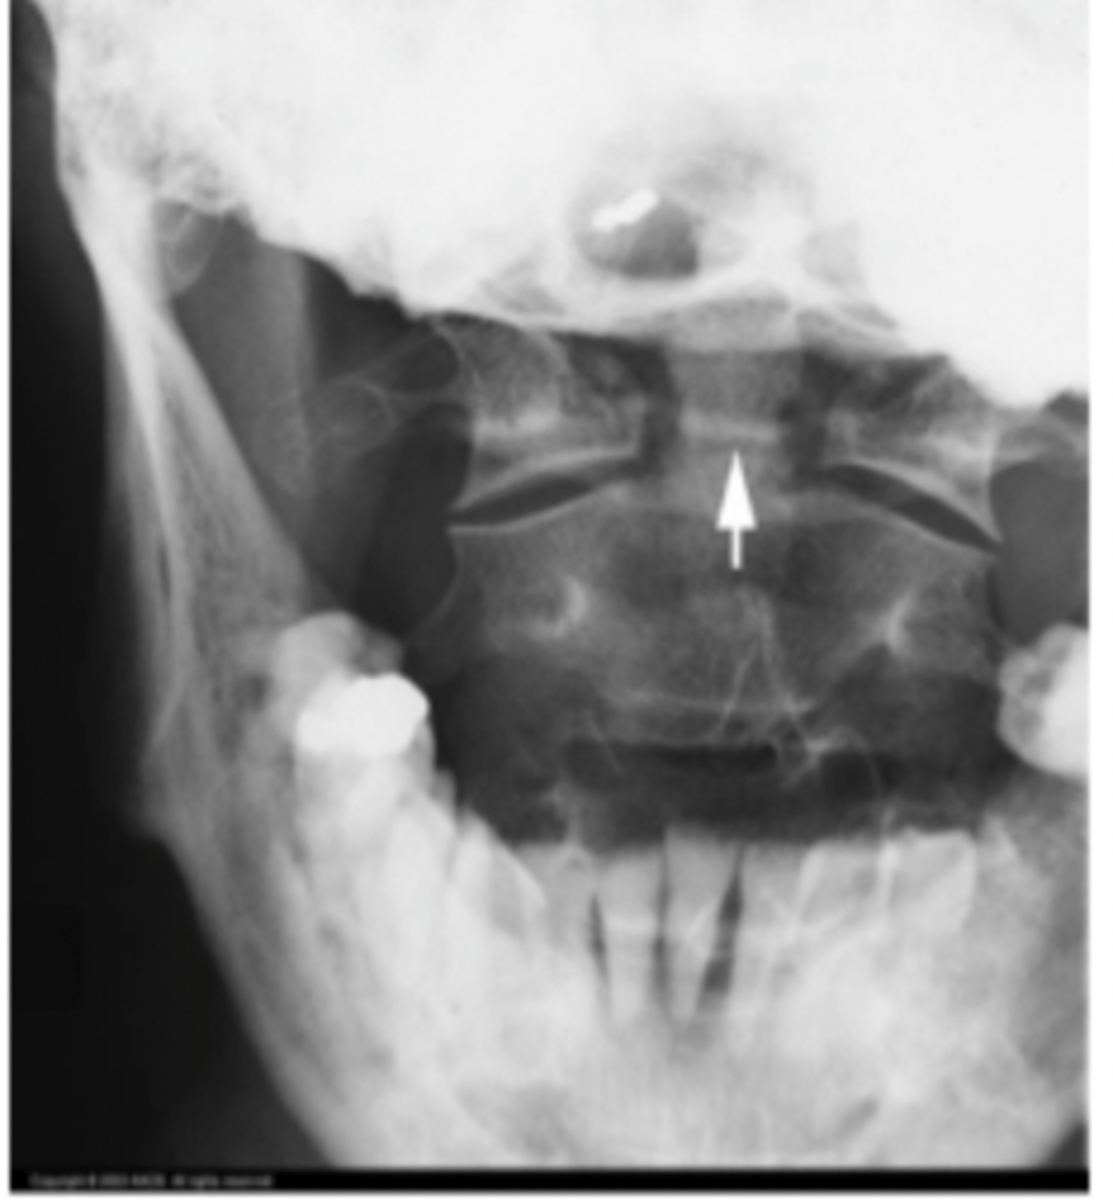

What view is this? What is it great for viewing?

AP open-mouth

Odontoid fx